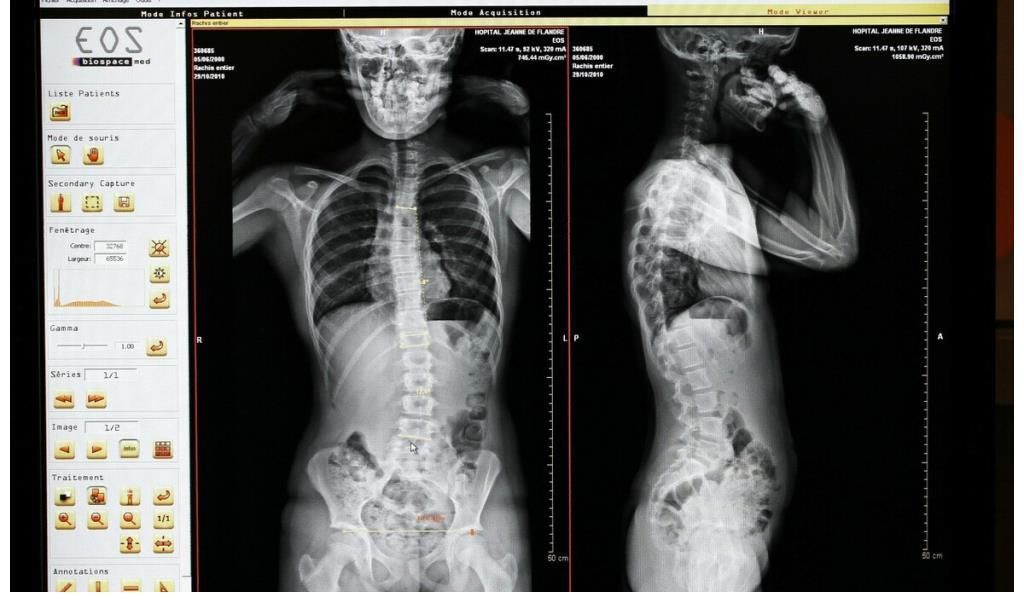

骨质疏松相信大家都不陌生,这是一种常见的老年慢性病。骨质疏松又叫骨质疏松症,是多种原因引起的骨病,病症发生,以单位体积内骨组织量减少为特点进行代谢性骨病变。

骨质疏松会给生活带来巨大的变化,变矮驼背会影响生活质量,腰酸背痛也会出现恶化的情况。如果发生了骨折,甚至可能带来长期残疾的风险。在我国大约有9000万的骨质疏松患者,这就表明我们应该多关注这种骨骼疾病。